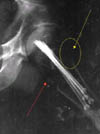

Όταν οι μετεμμηνοπαυσιακές γυναίκες διακόπτουν την ορμονική θεραπεία, η οστική τους πυκνότητα μειώνεται και αυξάνεται ο κίνδυνος κατάγματος ισχίου, σύμφωνα με αμερικανική μελέτη που δημοσιεύεται στο επιστημονικό έντυπο Menopause.